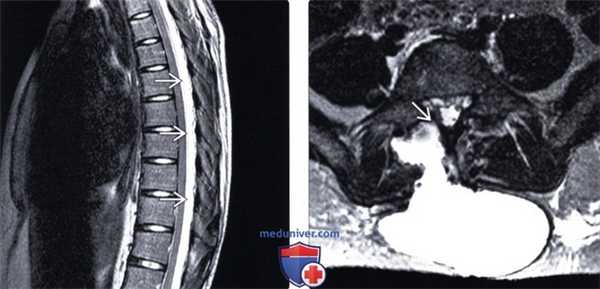

(Слева) STIR МР-И сагиттальная проекция: оскольчатый взрывной перелом тела L5 с формированием крупного заднего псевдоменингоцеле вследствие разрыва твердой мозговой оболочки и истечения СМЖ. Травматический спондилолистез также стал причиной выраженной деформации дурального мешка на уровне повреждения.

(Справа) Т2-ВИ, сагиттальная проекция: перелом зубовидного отростка I типа и большого объема полость в вентральной части эпидурального пространства, заполненная жидкостью, оттесняющая дуральный мешок кзади и приводящая к незначительной компрессии шейного отдела спинного мозга. (Слева) На аксиальном КТ-срезе с КУ у пациента, которому недав -но была выполнена передняя дискэктомия шейного отдела позвоночника и спондилодез, определяется крупное псевдоменингоцеле, распространяющееся от уровня выполненной дискэктомии в превертебральное пространство и затем в ткани кнутри от сонной артерии и яремной вены.